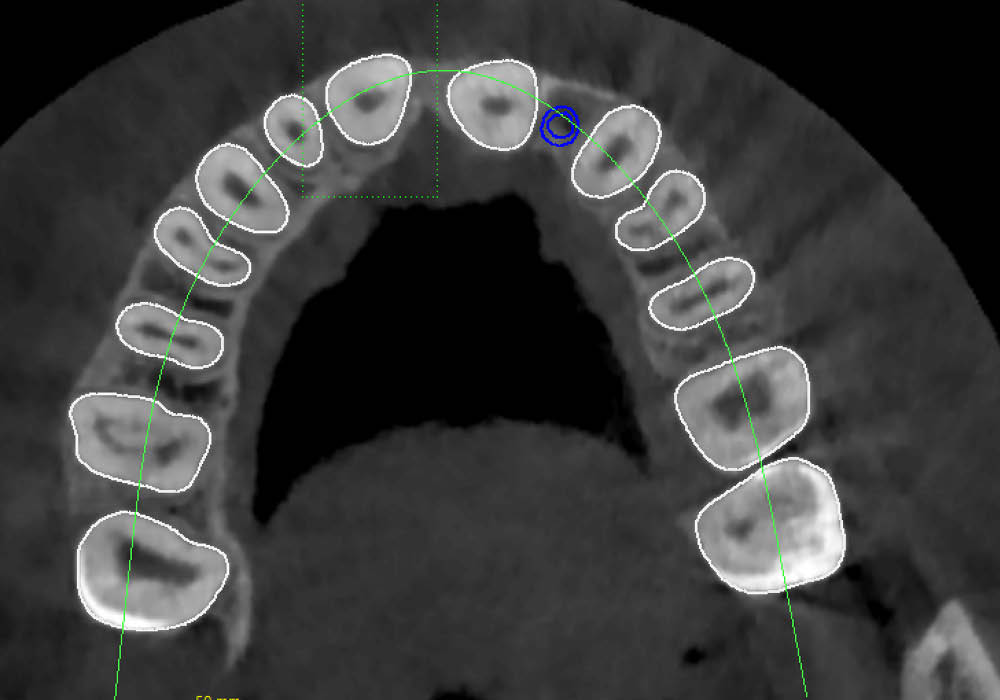

La segmentazione dei dati CBCT è stata effettuata partendo da un file DICOM.

L’utilizzo dell’intelligenza artificiale ha permesso di automatizzare la separazione e la ricostruzione tridimensionale delle strutture anatomiche, facilitando l’elaborazione e garantendo maggiore precisione nella valutazione iniziale.

La pianificazione chirurgica ha previsto un’analisi tridimensionale dettagliata del sito implantare, valutato sia da angolazioni multiple sia in visione frontale diretta.

L’obiettivo era quello di definire con precisione posizione, profondità e inclinazione dell’impianto, tenendo conto della vicinanza delle radici adiacenti e della necessità di preservare un adeguato spessore vestibolare.

Questa fase ha permesso di anticipare eventuali criticità e assicurare l’inserzione corretta all’interno dei limiti anatomici disponibili.